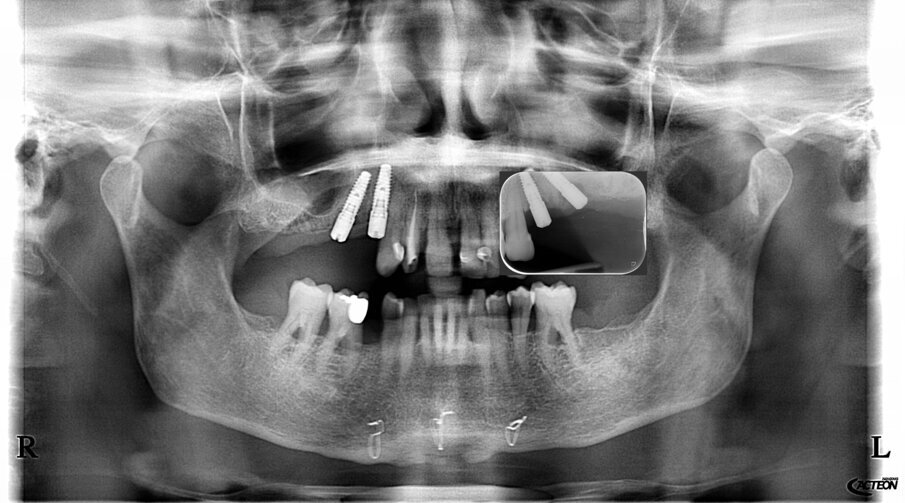

Fig. 47_Inserimento impianto.

Figg. 48, 49_Inserimento impianto.

Fig. 50_Controllo radiografico.